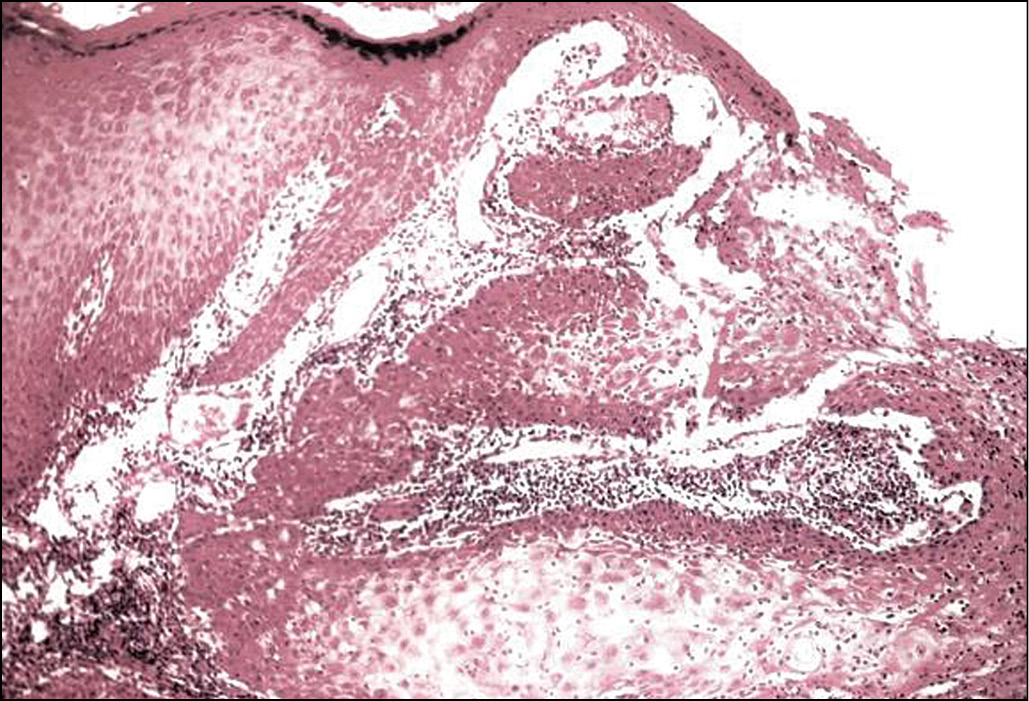

Рис. 2. Патоморфологическая картина кератоакантомы: акантолитические тяжи эпидермиса погружены в дерму на разную глубину, выражены явления псевдоэпителиоматозной гиперплазии. Окраска гематоксилином и эозином. Ув. 200

Результат гистологического исследования: патоморфологическая картина представлена пролиферирующими акантолитическими тяжами эпидермиса, погружёнными в дерму на различную глубину, с явлениями псевдоэпителиоматозной гиперплазии (рис. 2).